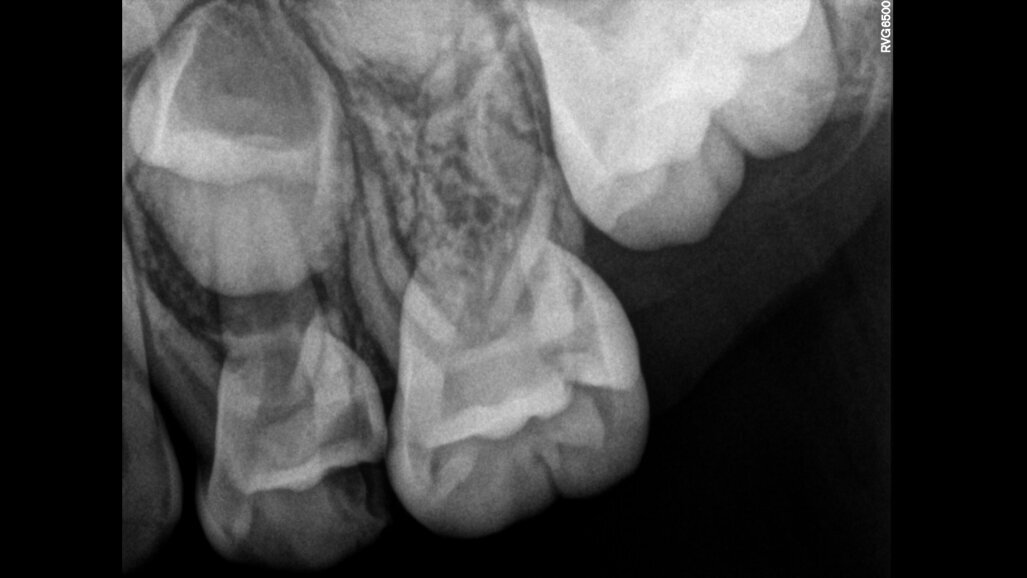

צילומי רנטגן, או הדמיית רנטגן, הם עזר אבחוני הכרחי ברפואת שיניים שכן הם מאפשרים זיהוי של מחלות וחריגות אחרות, כמו גם מעקב אחר התקדמות המחלה.

צילומי רנטגן, או הדמיית רנטגן, הם עזר אבחוני הכרחי ברפואת שיניים שכן הם מאפשרים זיהוי של מחלות וחריגות אחרות, כמו גם מעקב אחר התקדמות המחלה. הם גם מאפשרים לרופאי שיניים להמליץ למטופליהם על הטיפול המתאים ביותר במידת הצורך, כגון מילוי חללים, כתרים לשיניים, שתלים, uעוד.

כדי להבטיח שימוש נכון בצילומי רנטגן ובמידת הצורך, הסוכנות הבינלאומית לאנרגיה אטומית (סבא"א), שבסיסה בוינה, אוסטריה, פרסמה לאחרונה דו"ח בטיחות על הגנת קרינה ברדיולוגיה דנטלית. הדו"ח מספק הדרכה לרופאי שיניים ולצוותי שיניים רחבים יותר על שימוש נכון בקרני רנטגן ברפואת שיניים.

בעוד שהמינון היעיל להדמיית שיניים נפוצה משתנה מאוד, המינון של Cone Beam Computed Tomography (CBCT) המשמש להדמיה תלת מימדית דורש כמויות גדולות יותר, וטומן בחובו סיכון לנזק כתוצאה מהשפעות שליליות. כדי להפחית סיכונים, הפרסום החדש של סבא"א כולל הנחיות מפורטות להצדקת הליכים רדיולוגיים דנטליים ואופטימיזציה של ההגנה והבטיחות מקרינה עבור מטופלים וצוותי שיניים.